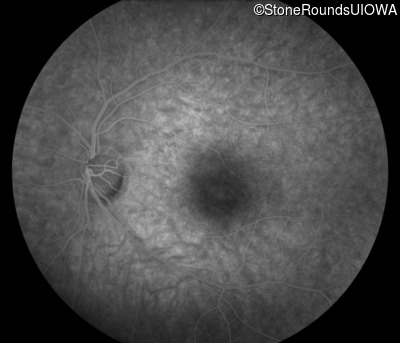

Infrared Fundus Photograph - Left - 20/40

Exemplar